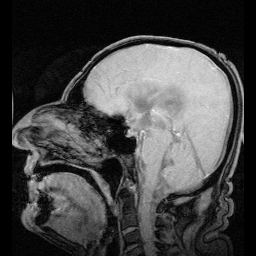

Behalve het hersenvocht tussen de hersenvliezen, is er een aantal ventrikelstelselstructuren ìn de hersenen gevuld met hersenvocht:

- de zijventrikels, ventriculi laterales

- het foramen van Monro, foramen Monroi

- de derde ventrikel, ventriculus tertius

- het aquaduct van Sylvius, aquaeductus Sylvii

- de vierde ventrikel, ventriculus quartus

- het centrale kanaal in het ruggenmerg, canalis centralis medullae spinalis

De aanmaak van hersenvocht vindt plaats door filtratie van bloed in de plexus choroideus. Deze ligt onder andere in de zijventrikels. Vanaf hier stroomt het via het foramen van Monro naar de derde ventrikel, om vervolgens via het aquaduct van Sylvius in de vierde ventrikel en het centrale kanaal terecht te komen. Vanuit hier stroomt het door het foramen van Luschka en het foramen van Magendie. Dan komt de vloeistof in de ruimte tussen het spinnenwebvlies en het zachte hersenvlies, de subarachnoïdale ruimte. Het hersenvocht komt uiteindelijk boven in de schedel terecht, in de sinus sagittalis superior, waar het door cellen wordt opgenomen. Deze cellen worden de granulationes arachnoideae of granula meningica[3] genoemd. Na opname wordt het vocht weer door het bloed opgenomen.